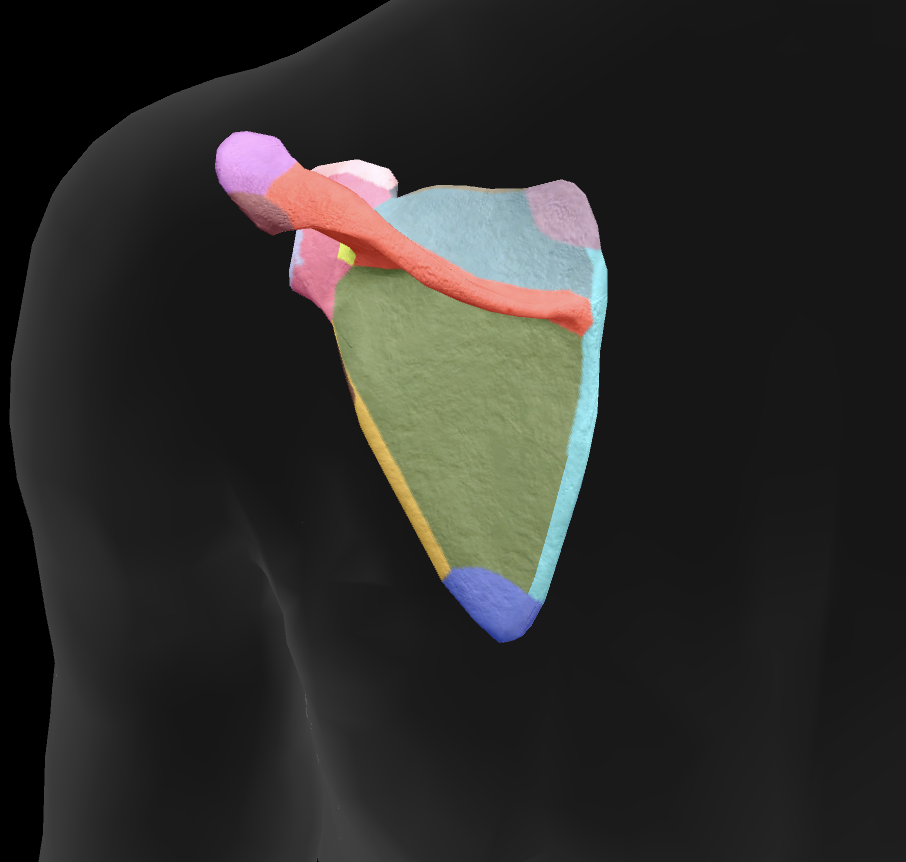

What bone is this?

scapula

What is this boney landmark?

spine of scapula

What is this boney landmark?

supraspinous fossa

What is this boney landmark?

infraspinous fossa

What is this boney landmark?

acromion process

What is this boney landmark?

superior angle

What is this boney landmark?

inferior angle

What is this boney landmark?

lateral border

What is this boney landmark?

medial border

What is this boney landmark?

subscapular fossa

What is this boney landmark?

spinoglenoid notch

What is this boney landmark?

glenoid fossa

What is this boney landmark?

supraglenoid tubercle

What is this boney landmark?

infraglenoid tubercle

What is this boney landmark?

coracoid process